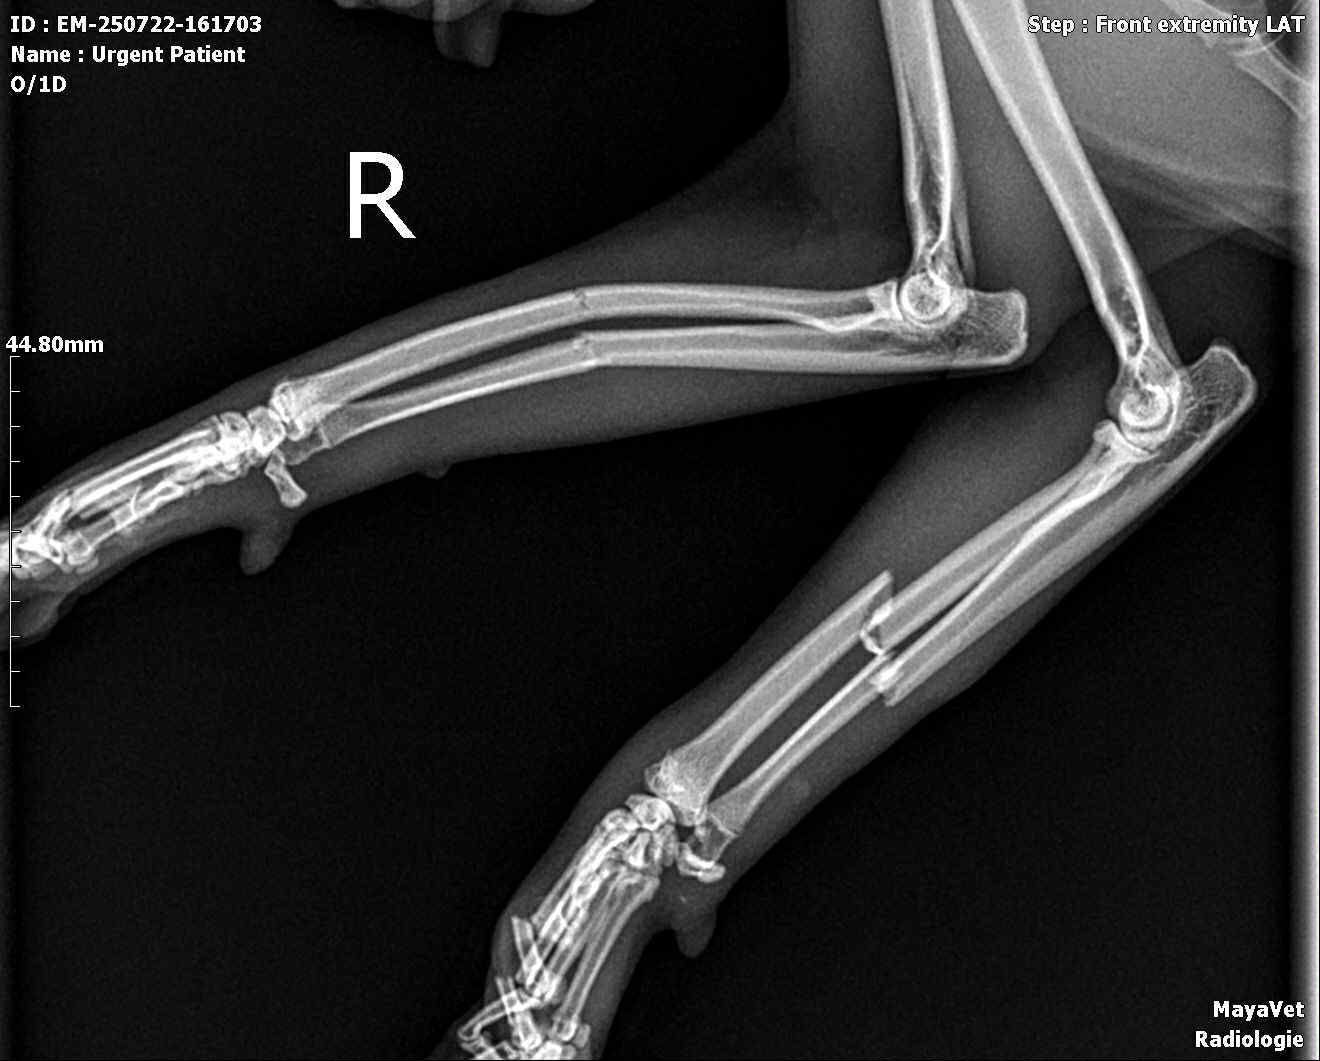

Din păcate, radiografiile au confirmat ceea ce bănuiam: ambele membre anterioare fracturate la nivelul radiusului si al ultei , iar Misha are nevoie de o intervenție chirurgicală ortopedică pentru a putea merge din nou și, mai ales, pentru a trăi fără durere.